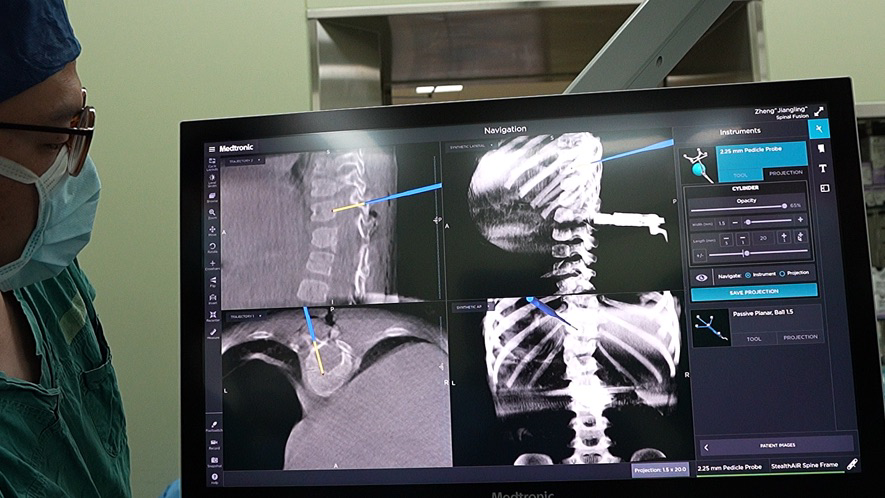

这款由美敦力导航联合O型臂的技术,是目前全球最顶尖骨科智能导航和术中三维影像技术。相比传统C型臂、G型臂,O型臂的优点在于:13秒完成多角度三维图像扫描,大幅度减少辐射剂量;高清、完整、实时的三维影像导航,提供更精准的置钉定位,缩短手术时间

术中O型臂3D导航系统,利用最新引进的3D立体影像系统在术中为医师提供3D立体影像,术前规划模拟出立体重组影像与各层面影像,为主刀医师计划最佳的手术路径。术中还可将患者放进类似电脑断层扫描影像(CT)的仪器中,用完整360度自动环型扫描取像,即时更正路径规划与导航,避免伤害到周围的神经血管等重要器官组织,大大提高患者手术安全、准确定位、减少风险及并发症的发生。